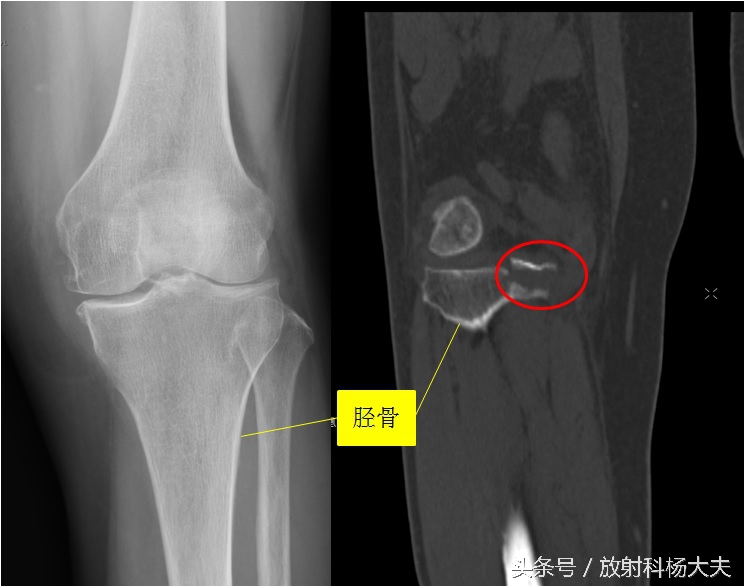

比如下图的X线片,发生在胫骨平台的骨折,很难发现。但做了CT,就比较容易了,如图中的红圈。

关键的一步是谁想到建议做CT。有的时候是有经验的骨科大夫,根据体检,高度可疑胫骨平台骨折,但X线却没发现异常,此时会建议病人做CT或者MRI。有的时候是有经验的放射科大夫,读片的时候总觉得胫骨平台有的地方不对劲,再去查查体,怀疑胫骨平台骨折,会建议做CT或MRI。